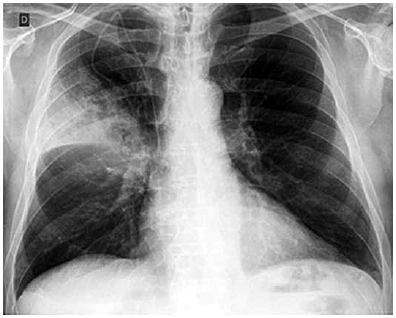

RX de tórax:

Ao exame, encontra-se em REG, consciente e orientado, desidratado ++/4+; temperatura axilar 38 oC; FR 22 irpm, PA 120 x 70, ritmo cardíaco regular em 2 tempos sem sopros; FC 124 bpm, MV presente com EC em base e 1/3 médio HTD, saturação O2 92% em ar ambiente, dextro 340 mg/dL.